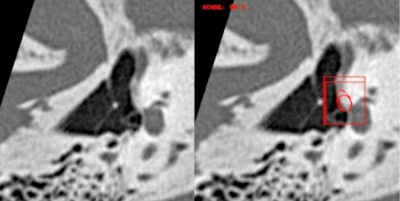

45-year-old woman with predominantly right-sided unilateral conductive hearing loss. Double oblique view of the stirrup. Stapedial otosclerosis with isolated isodense filling of the fissula ante fenestram detected by the Oto-Med recognition tool. Courtesy of

45-year-old woman with predominantly right-sided unilateral conductive hearing loss. Double oblique view of the stirrup. Stapedial otosclerosis with isolated isodense filling of the fissula ante fenestram detected by the Oto-Med recognition tool. Courtesy of e-Quotidien, daily newspaper of Journées Francophones de Radiologie (JFR).

Regarding imaging, deep learning already allows clinical applications ranging from the automatic segmentation of anatomical structures, recognition of small pathologies such as otosclerosis, through to medical education, and even surgical planning with, in particular, facial nerve tracking. For otosclerosis, real performance results are at least equivalent to expert radiologists, even at stages I and II, also allowing differential diagnoses such as stapedial malformation or chronic otitis.

In a study using the algorithm developed using Cleverdoc tools and led by Oto-Med, the results of external validations of 124 cases studied on multibrand CTs, with otosclerosis confirmed surgically (Figure 2), were 96.6%, 95.3%, 95%, and 97% respectively for sensitivity, specificity, positive predictive value (PPV), and negative predictive value (NPV). The other tools developed relate to malformative and cholesteatoma pathologies and vestibular MRI. The future also lies in the integration of other biomarkers, whether clinical, biological, electrophysiological, anatomopathological, or genomic, to improve patient care.